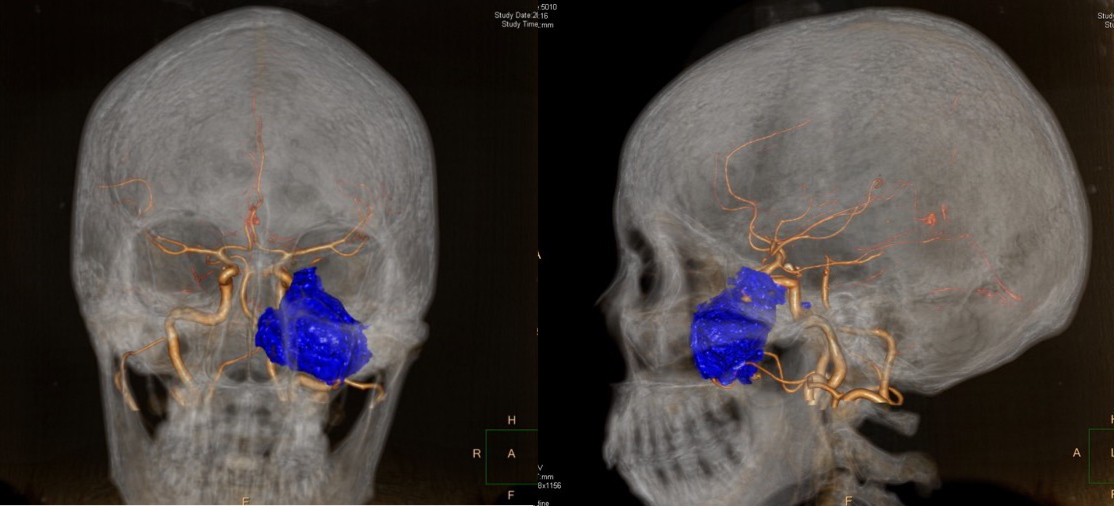

此病例肿瘤较大,且侵犯左侧上颌窦外侧壁与腭骨垂直板,经单入路不能完全切除肿瘤组织,故采用经鼻-上颌窦/腭骨垂直板联合入路(如图14-15)。针对翼腭窝肿瘤,神经内镜视野下尽可能的减少翼腭窝内血管以及神经的损伤,更有效的去除肿瘤组织。

图14.灌注标本,内镜下经鼻-腭骨垂直板入路

图15.灌注标本,内镜下经鼻-上颌窦入路